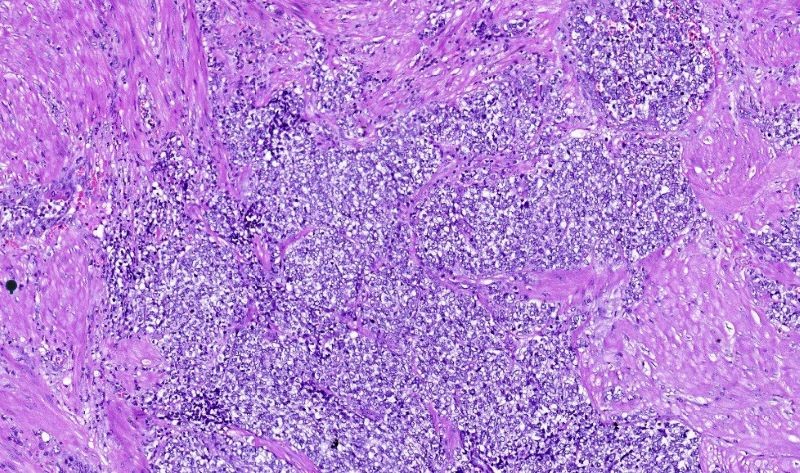

Hình ảnh mô bệnh học cho thấy các tế bào u mang các đặc điểm của tế bào ác tính đang tăng sinh mạnh mẽ

Kết quả chụp MRI kết luận bệnh nhân có đa u xơ tử cung. Bệnh nhân được phẫu thuật cắt tử cung bán phần và hai phần phụ. Khối bệnh phẩm kịp thời được gửi đến Trung tâm Giải phẫu bệnh Medlatec thực hiện xét nghiệm hóa mô miễn dịch nhằm chẩn đoán xác định bản chất u.

Tại đây, sau khi phân tích hình ảnh vi thể kết hợp kinh nghiệm lâm sàng, các bác sĩ giải phẫu bệnh đã chỉ định một số dấu ấn cần thiết để đi đến kết luận Sarcoma đệm bào độ cao - một loại ung thư rất hiếm gặp trong lâm sàng. Như vậy, bản chất khối bệnh phẩm được chẩn đoán u xơ tử cung trước đó thực chất là Sarcoma.

Giải thích về bệnh lý Sarcoma, bác sĩ Nguyễn Văn Tuấn cho biết: “Sarcoma đệm bào là u trung mô ác tính tại tử cung, nguồn gốc của tế bào u xuất phát từ tế bào đệm của nội mạc tử cung. Sarcoma đệm bào là loại Sarcoma phổ biến thứ 2 sau Sarcoma cơ trơn, tỷ lệ hiếm gặp, <1% trong các loại u ở tử cung và chiếm khoảng 25% các trường hợp Sarcoma tử cung. Bệnh lý thường có tiên lượng xấu nếu không được can thiệp điều trị kịp thời. Trong đó, phẫu thuật cắt tử cung toàn bộ có vai trò chủ yếu trong điều trị triệt căn khối u”.